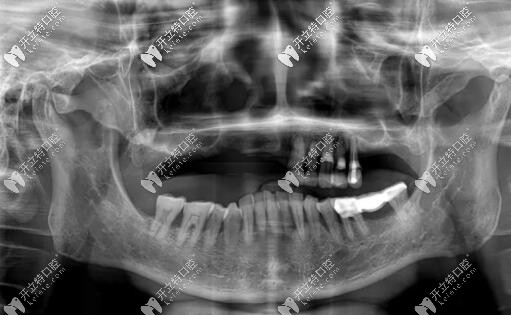

惠先生種植方案:前期A(yíng)LL-ON-4即刻負(fù)重,后期上頜竇外提升,同期植入兩顆種植體,做ALL-ON-6,馬龍一體橋。

目前已完成ALL-ON-4即刻負(fù)重,通過(guò)手術(shù)情況來(lái)看,效果確實(shí)比較好,作為一位地道老陜?nèi)?,惠先生的感激之情溢于言表?/p>